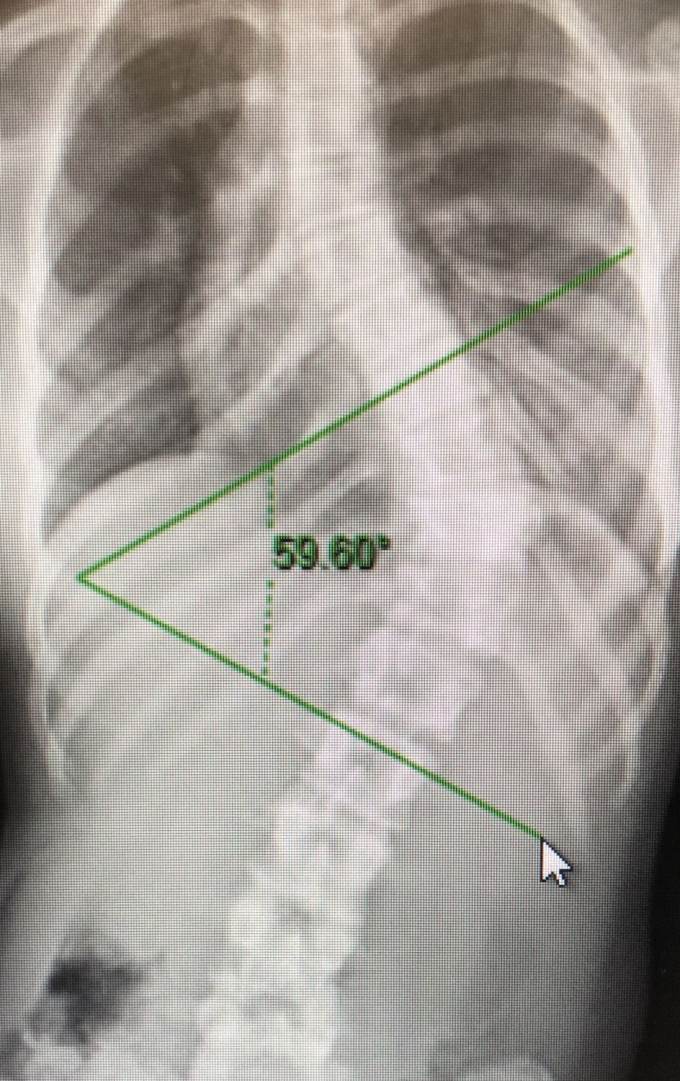

Before the outbreak this year, Leilani's parents brought her for a routine examination. The child's scoliosis had exceeded 60 degrees. It was necessary to perform surgery to correct the deformity, lighten her spinal pain and avoid any further progression of the problem. Without intervention, her cardiopulmonary function would be severely damaged. We also invited experts from other hospitals to consult with us on tailoring an operation plan for Leilani. Leilani's parents referred to their German experts and compared the options. Considering that Leilani was very familiar with the hospital environment and that she had faith in the patience and care of our medical team, they finally agreed to have the scoliosis surgery in our hospital.

Leilani’s X-ray examinations (before & after operation)